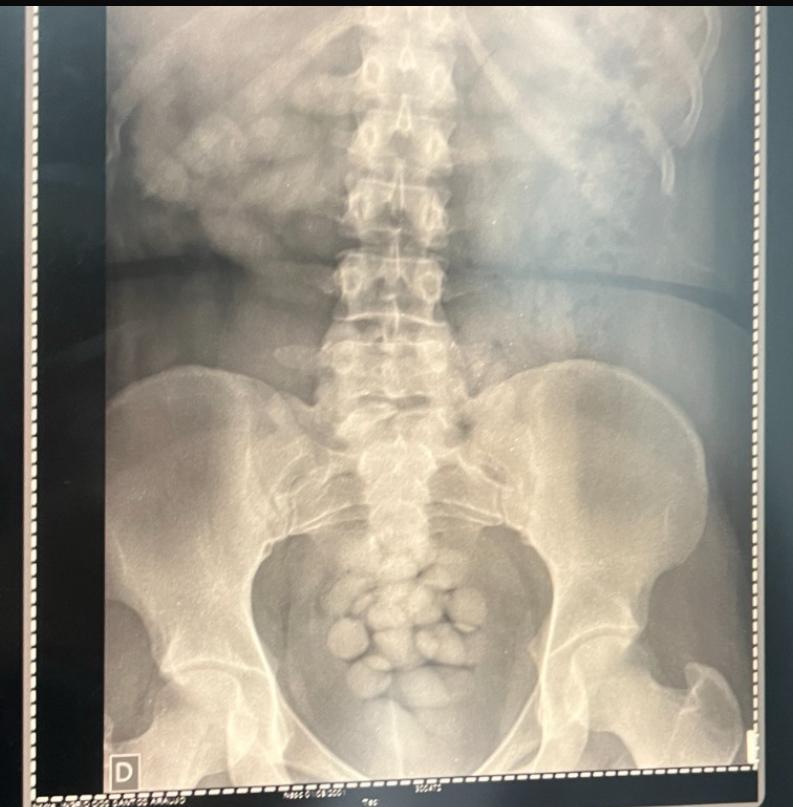

A investigação teve início em outubro de 2024, após a prisão em flagrante de uma jovem de 20 anos que tentava embarcar para Paris com 1,3 kg de cocaína engolida em cápsulas. A descoberta levou os agentes a um esquema estruturado, com ramificações no Brasil e no exterior.